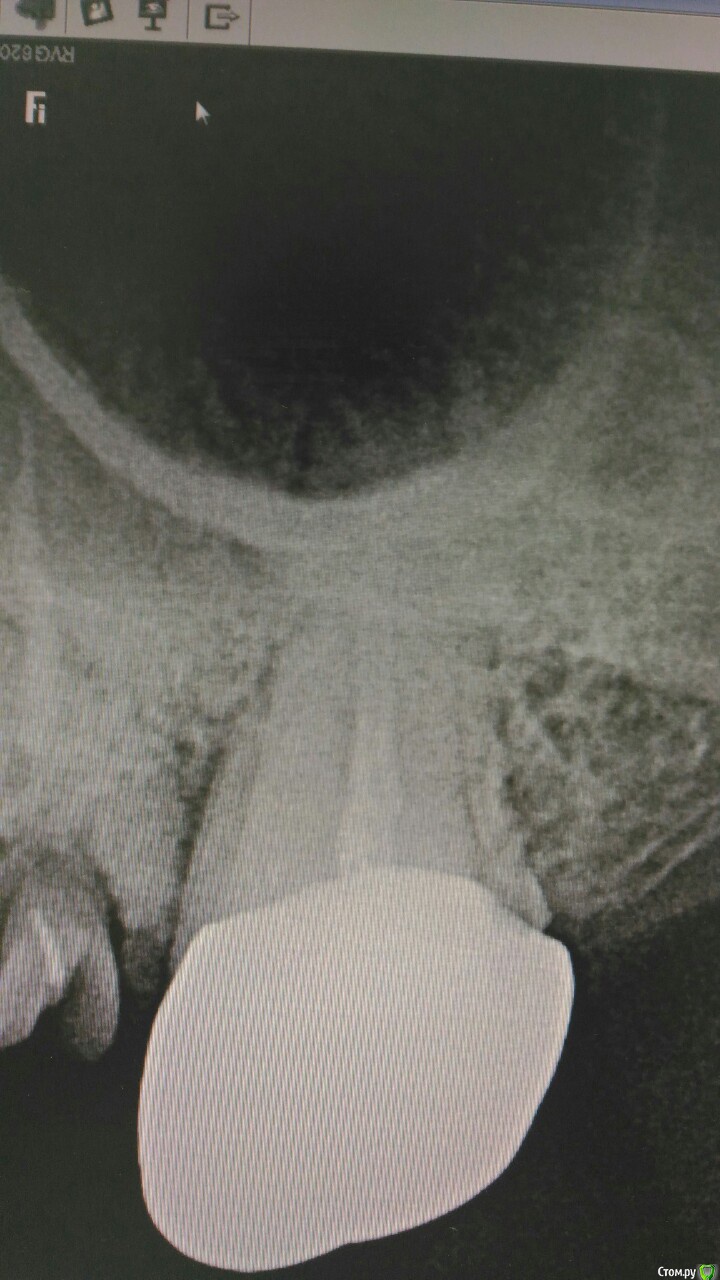

Кларита Опубликовано 18 марта, 2019 Поделиться Опубликовано 18 марта, 2019 Ситуация следующая: пацинетку направили из другой клиники к ортопеду,(22 расцементировка мк коронки с отломо культи 22 зуба, расцементировка мк моста 23-26(26-корни, мост давно носится пацинкой на Кореге, 27-хр.периодонтит под металлической коронкой.22 похоже предыдущий оператор перфорировал и с формулировкой -распломбировать с/в штифт не удалось-направил ко мне).Ситуация осложняется тем, что отлом 22 зуба произошел после удара и пациентка собирается на обидчика в суд подавать. От КЛКТ отказалась-дорого(со слов направившего коллеги).Вопрос-что бы вы делали на месте ортопеда ? как правильно описать карту? или отправить от греха подальше? Ссылка на комментарий